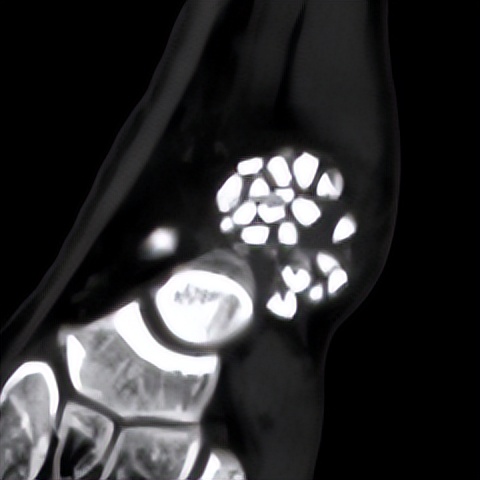

林先生来到省二医后,何河北医生为其进行了详细查体,检查后确诊为踝关节不稳+滑膜软骨瘤

何河北制定了详细的手术方案,为患者开展踝关节镜下滑膜软骨瘤取出术+距腓前韧带重建术。他从患者踝关节中取出32颗“珍珠”(关节游离体),然后进行踝关节外侧韧带重建。

▲术前可见踝关节前方有大量“珍珠”。